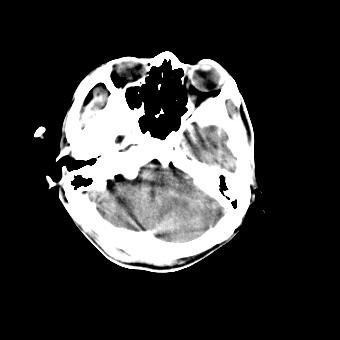

标题: CT16478:男 头晕 恶心 呕吐 [打印本页]

标题: CT16478:男 头晕 恶心 呕吐

病人不合作,图像质量差,右额叶及后纵裂可见高密度影,建议复查。

1.额叶显示密度不均匀,且右侧内见小片稍高密度影, 图像效果差些,不好定?

2.纵裂密度增高,部分脑回密度似乎也增高,蛛网膜下腔出血。

右额叶小片状高密度灶,周围有水肿带,为脑出血;是否有外伤史?若没有,则考虑肿瘤——胶质瘤出血可能性大。

病人不合作,图像模糊,大脑镰及纵裂池后部密度增高;考虑:蛛血?

右额叶片状低密度灶,其前内侧小片状略高密度,首先考虑胶质瘤

另外恶心呕吐多久,临床有无发热,年龄多大?不排除脑炎的可能

[quote]以下是引用叶子123在2008-11-13 9:55:00的发言:[br]患者因煤气中毒入院,临床及ct均诊断一氧化碳中毒性脑病[br][br]